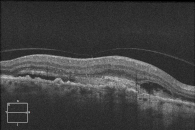

Die Unterscheidung zwischen einer trockenen und einer feuchten Makuladegeneration kann mit einer Fluoreszenzangiographie oder einer optischen Kohärenztomographie (OCT) erfolgen.

Die OCT-Untersuchung ist ein sogenanntes nichtinvasives Verfahren, ein Kontrastmittel ist nicht erforderlich. Außerdem erhalten wir mit dieser Untersuchung zusätzliche Erkenntnisse über den Zustand der einzelnen Netzhautschichten und des Sehnerven.